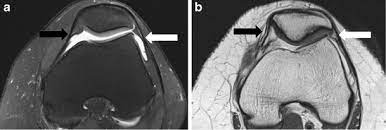

The typical injury pattern is a tear of the medial patellofemoral ligament (mpfl) and bone bruises of the patella and the lateral femoral condyle. When a tear is caused by a medical condition — like tendinitis — the tear usually occurs in the middle of the tendon. Upon flexion of the knee, however, a shortened lateral retinaculum will come under excessive stress as the patella is drawn in the trochlea and the iliotibial band pulls posteriorly on the already shortened lateral retinaculum. Current right knee medial meniscus tear; When this happens, you may face a recovery time of weeks to months, depending on the grade of the mcl.

The lateral retinaculum is a ligament that helps hold your patella, or kneecap, in place. The first step in treating a torn meniscus is getting the injury examined by a physician who specializes in orthopedics. The knee was let to bend down to 90 degrees, and this had excellent repair. Despite a decrease in frequency related to improvements in implant design and surgical technique, they still account for about 10% of all tka complications 2. After er doc's saying i must have broken some bone/acl/whatever else, the ortho saying he thought i may have torn my quad tendon, i found out it was none of the above. The surgical technique achieved reinforced reattachment of the torn region of the medial retinaculum for improved patellar support and stabilization. It thickens as it inserts onto the. The ensuing loss of medial restraint favors future patellar dislocations, especially if additional risk factors are present. Pain on the inside of the knee which may be of sudden onset but can also occur gradually. This repaired the quadriceps tendon down anatomically. The typical injury pattern is a tear of the medial patellofemoral ligament (mpfl) and bone bruises of the patella and the lateral femoral condyle. But because of the ligament's location, adequately stretching it can be difficult. The patellar tendon often tears at the place where it attaches to the kneecap, and a piece of bone can break off along with the tendon.

The typical injury pattern is a tear of the medial patellofemoral ligament (mpfl) and bone bruises of the patella and the lateral femoral condyle.

the mcl attempts to resist the knee bending sideways and tears if the force is too great. Stephen pribut's running injuries website. Pain on the inside of the knee which may be of sudden onset but can also occur gradually. The medial and lateral patellar retinaculum are on their respective sides of the patella and are continuous with the vastus fascia to the tibia and the patella. Patellar contusions and avulsion fractures arealsoidentified inupto41% ofpatients i121.thepatellar injuries areadjacent tothe attachment ofthemedial retinaculum and tend toinvolve themedial andinferior aspects ofthebone. The typical injury pattern is a tear of the medial patellofemoral ligament (mpfl) and bone bruises of the patella and the lateral femoral condyle. A complete tear of the patellar tendon indicates a detachment of the kneecap from the shin and is accompanied by an inability to straighten your knee. The procedure is relatively new.